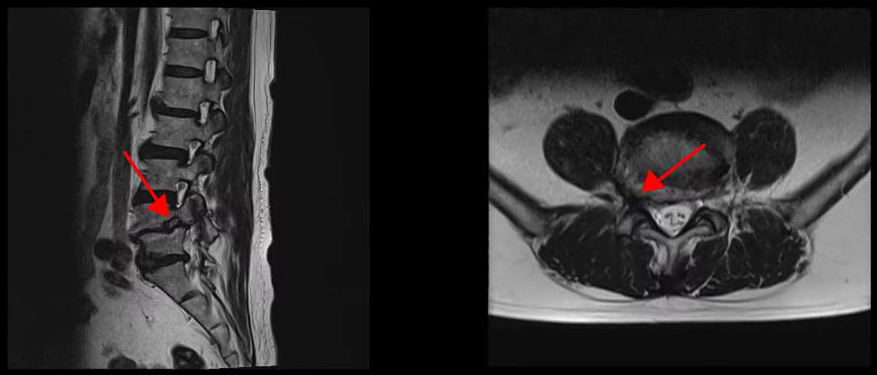

<4-5번 추간공협착증>

<4-5번 척추전방전위증>

<5-1번 디스크 파열>

이 환자분은 요추 4-5번 오른쪽에 심한 추간공협착증, 2단계의 전방전위증이 있으며, 특히 전방전위증으로 인해 추간공이 매우 좁아져 있습니다. 또 요추 5-1번 왼쪽에 디스크 파열이 있습니다.